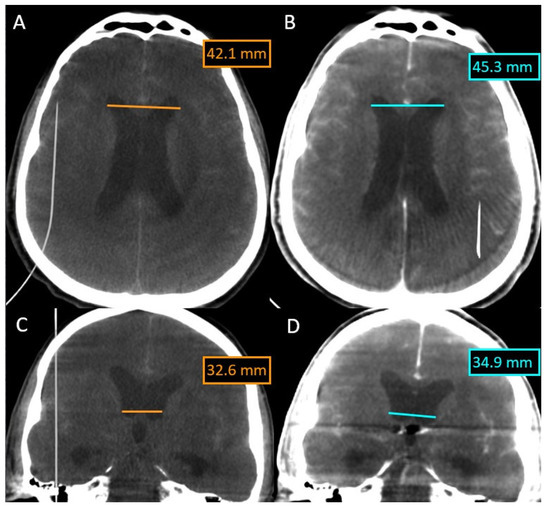

In this case, we overlaid two XperCT volumes (pre-operative and post-operative) to assess the evolution of hydrocephalus (Figure 5). We noticed that there is a difference of 2–3 mm between the size of the ventricles at the beginning and at the end of the intervention for the embolization of the aneurysm of the anterior communicating artery, a difference that appeared in 90 min.

Figure 5.

Evolution of hydrocephalus—comparison with the Overlay software. (A) XperCT volume axial preoperative. (B) XperCT volume axial postoperative. (C) XperCT volume coronal preoperative. (D) XperCT volume coronal post-operative.

The overlying was performed automatically and quickly, as we were dealing with volumes with numerous bone landmarks. No intraoperative bleeding was detected, either, and the hyperdense appearance at the end of the intervention was due to the contrast media.